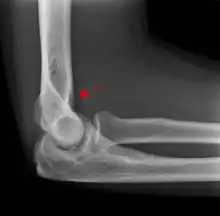

Fat pad sign

The fat pad sign, also known as the sail sign, is a potential finding on elbow radiography which suggests a fracture of one or more bones at the elbow. It is may indicate an occult fracture that is not directly visible. Its name derives from the fact that it has the shape of a spinnaker (sail).[1] It is caused by displacement of the fat pad around the elbow joint. Both anterior and posterior fat pad signs exist, and both can be found on the same X-ray.

In children, a posterior fat pad sign suggests a condylar fracture of the humerus. In adults it suggests a radial head fracture.

The fat pad sign is invaluable in assessing for the presence of an intra-articular fracture of the elbow. An anterior fat pad is often normal. However a posterior fat pad seen on a lateral x-ray of the elbow is always abnormal. The patient will be unable to flex their elbow and requires orthopaedic input.[2]